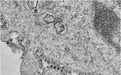

新型冠状病毒的薄片和扫描电镜显示了在培养中生长的受感染细胞的一部分,其病毒颗粒从细胞表面释放出来。

新型冠状病毒在细胞中生长的电子显微镜图像

与两名同事一起培育出病毒的香港大学病理学临床教授约翰·尼科尔斯(John Nicholls)表示,每一个受感染的细胞都会产生数千个新的传染性病毒颗粒,这些颗粒会继续感染新的细胞。

研究人员正在研究不同时间点的样本,以便更好地了解2019-nCoV病毒,也就是新型冠状病毒与其他冠状病毒复制的不同之处。

培养48小时后的冠状病毒电子显微镜图像